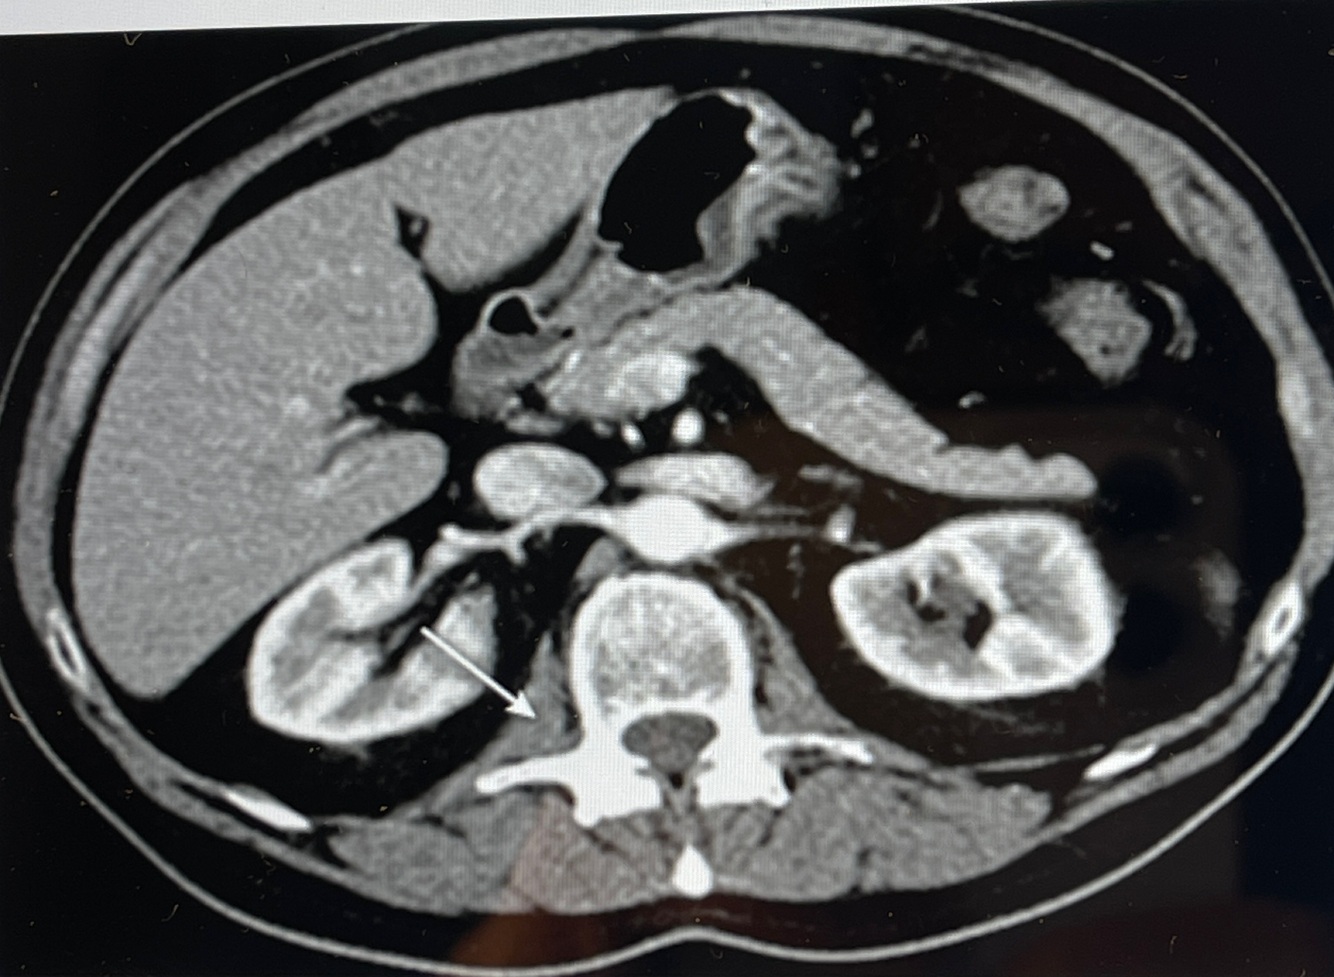

A

How well did you know this?